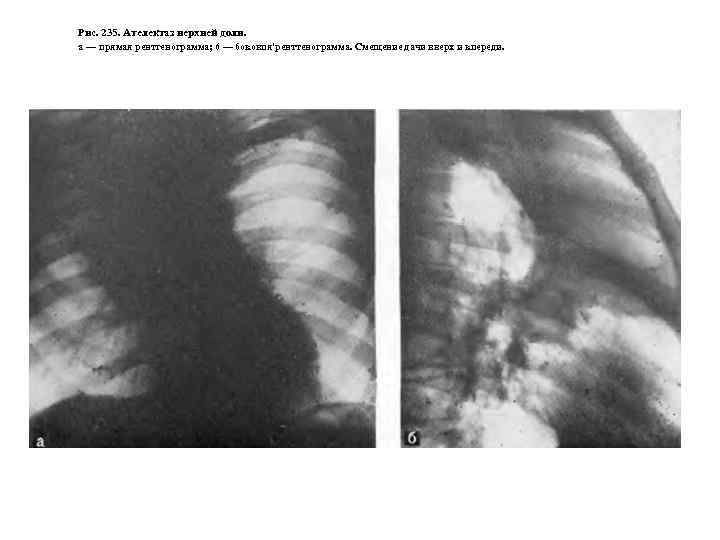

Рис. 235. Ателектаз нерхней доли. а — прямая рентгенограмма; 6 — боковпя'ренттенограмма. Смещение дачи вверх и кпереди.